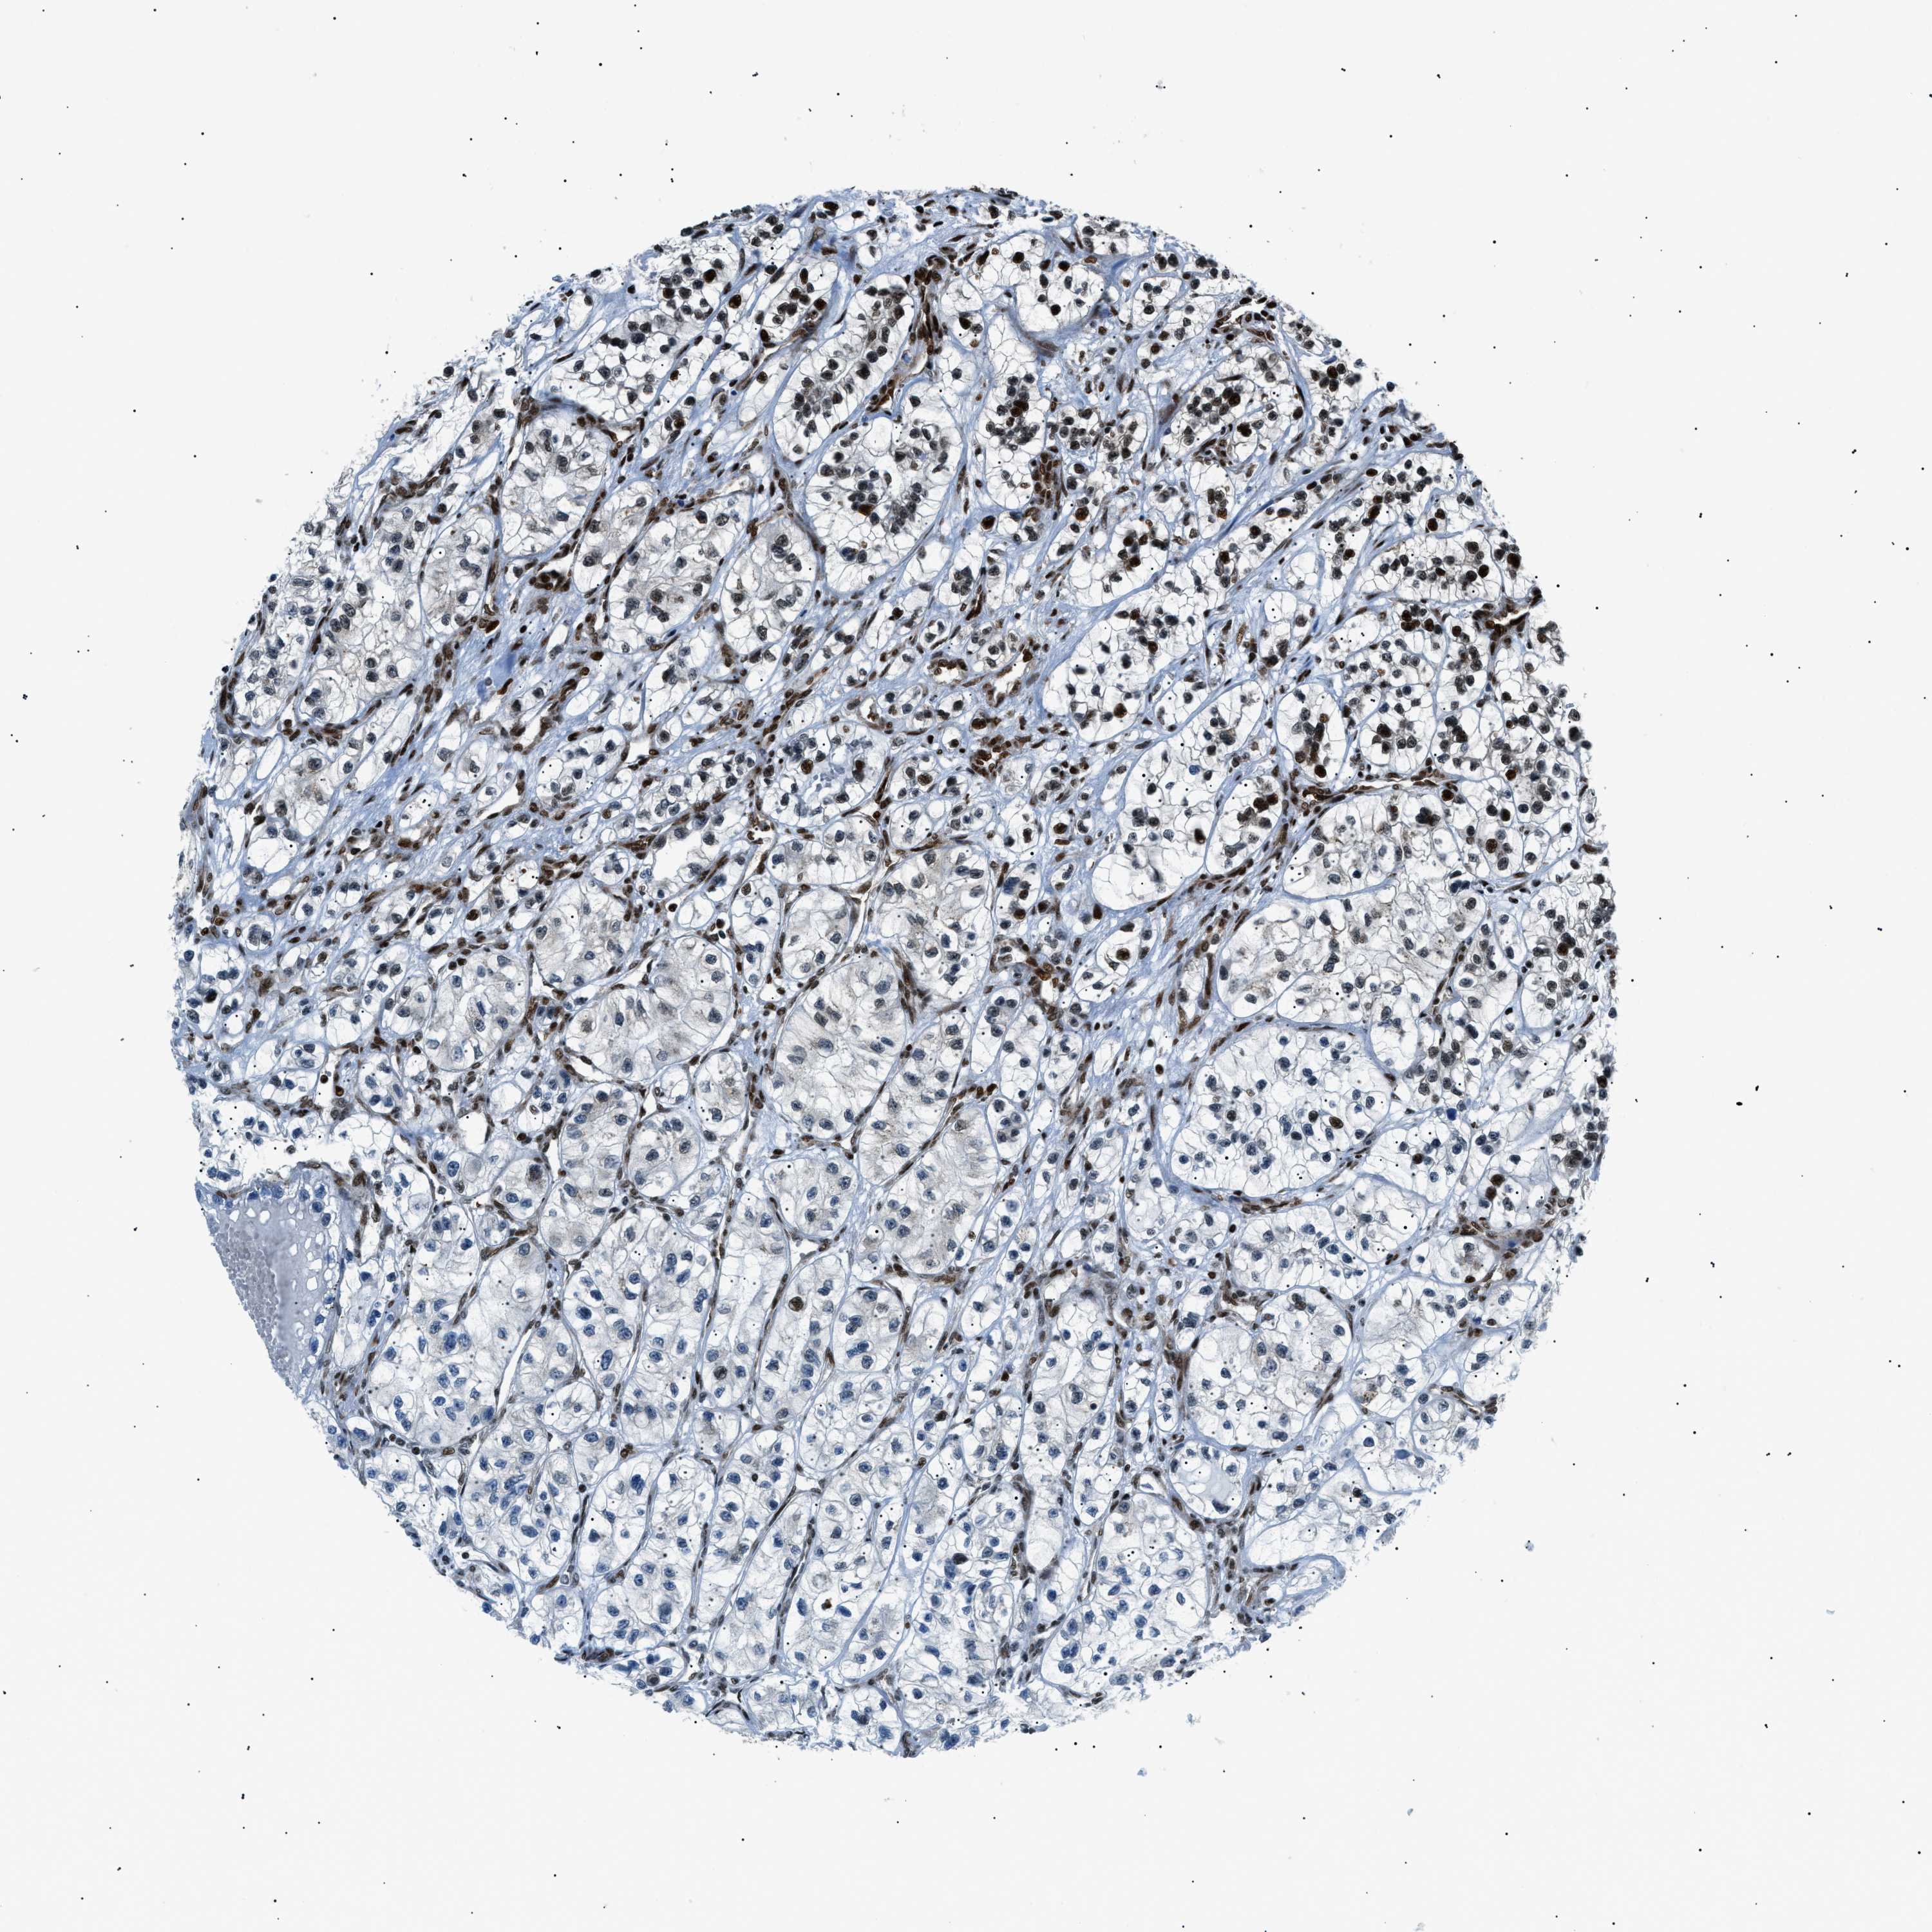

HNRNPK is validated prognostic, high expression is favorable in Kidney Renal Clear Cell Carcinoma (validation)

Best expression cut offi

Based on the FPKM value of each gene, patients were classified into two groups and association between prognosis (survival) and gene expression (FPKM) was examined. The best expression cut-off refers the FPKM value that yields maximal difference with regard to survival between the two groups at the lowest log-rank P-value. Best expression cut-off was selected based on survival analysis .

When clicking on this number, the vertical dashed line indicating cut-off, the interactive survival plot, and the Kaplan-Meier curve will be adjusted to show results based on the best expression cut-off.

: 384.93

P scorei

Log-rank P value for Kaplan-Meier plot showing results from analysis of correlation between mRNA expression level and patient survival.

N/A

5-year survival highi

5-year survival for patients with higher expression than the expression cutoff.

For melanoma and glioma, 3-year survival is shown.

5-year survival lowi

5-year survival for patients with lower expression than the expression cutoff.

Average pTPM 408.9

Number of samples 100